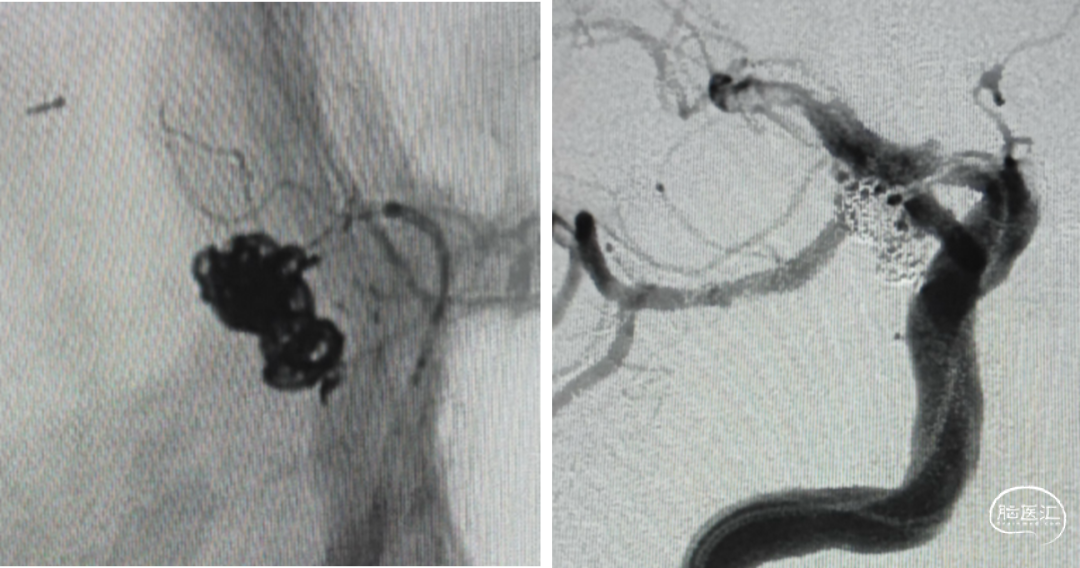

支架选择

LEO3.5x25 Atlas 3.0x15

Axium3d620;axium3d15

管2:target3d24